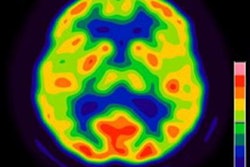

Representative images of (a) F-18 FDG uptake of visceral adipose tissue (VAT) according to the breast cancer recurrence status and (b) their corresponding magnified views. Image and caption courtesy of Scientific Reports licensed under CC BY 4.0 International License.By the median follow-up duration of 95.5 months, recurrence and distant metastases had occurred in 18 and 14 patients. Among these patients, high SUVmean-VAT was associated with shorter periods before breast cancer relapse.